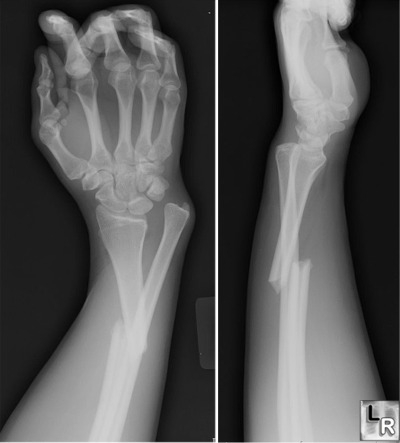

Yo estuve con el brazo derecho en forma de L mes y pico, casi dos, porque me fracturé el radio jugando a Baseball.

Algo así: